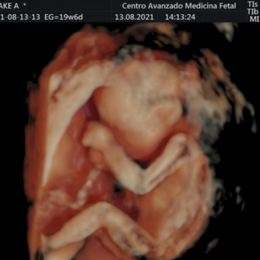

- Las formas nuevas de ecografía pueden proporcionar imágenes en 5-D.

¿Qué incluye el estudio?

- El estudio incluye 1 informe medico completo.

- 1 DVD con el estudio grabado.

- 1 CD para la computadora con todas las imágenes del estudio.

- 1 foto color ampliada en papel fotográfico color tamaño A4.

- Fotos blanco y negro impresas en el informe medico.